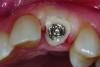

Fig 7. Blanching of the soft tissue.

Figure 7